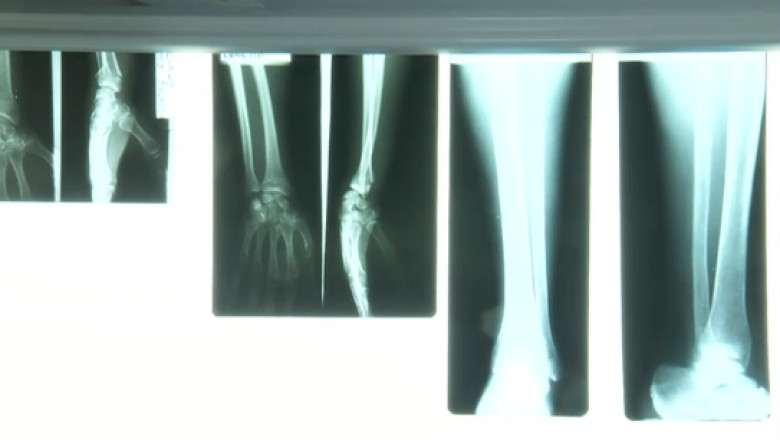

Medicii de la spitalul din Alba Iulia i-au recomandat unei fetițe de 5 ani cu mâna ruptă doar un unguent pentru dureri, deși îi făcuseră radiografie. Câteva ore mai târziu, părinții au dus copilul la Sibiu, unde medicii au stabilit că mâna este fracturată și trebuie pusă în ghips.

Le-a spus medicilor că are dureri insuportabile la mână, iar pediatrul i-a făcut o radiografie. A constatat că nu e vorba decât de o contuzie, așa că le-a spus medicilor să cumpere un unguent și să o maseze în zona dureroasă. Medicul le-a recomandat părinților ca, dacă durerile continuă, să ducă fata la Sibiu, unde e medic de specialitate.

Durerile au devenit și mai mari a doua zi, așa că părinții au dus fetița la spitalul din Sibiu. Un medic de acolo a constatat că copilul are fractură și i-a pus mâna în ghips.